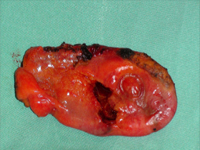

SurgeryGallbladder injuries occur in only 2.1-3.5% of patients undergoing laparotomy for injuries to the abdominal cavity and are almost always accompanied by injuries to other abdominal organs. Isolated injuries to the gallbladder are extremely rare.